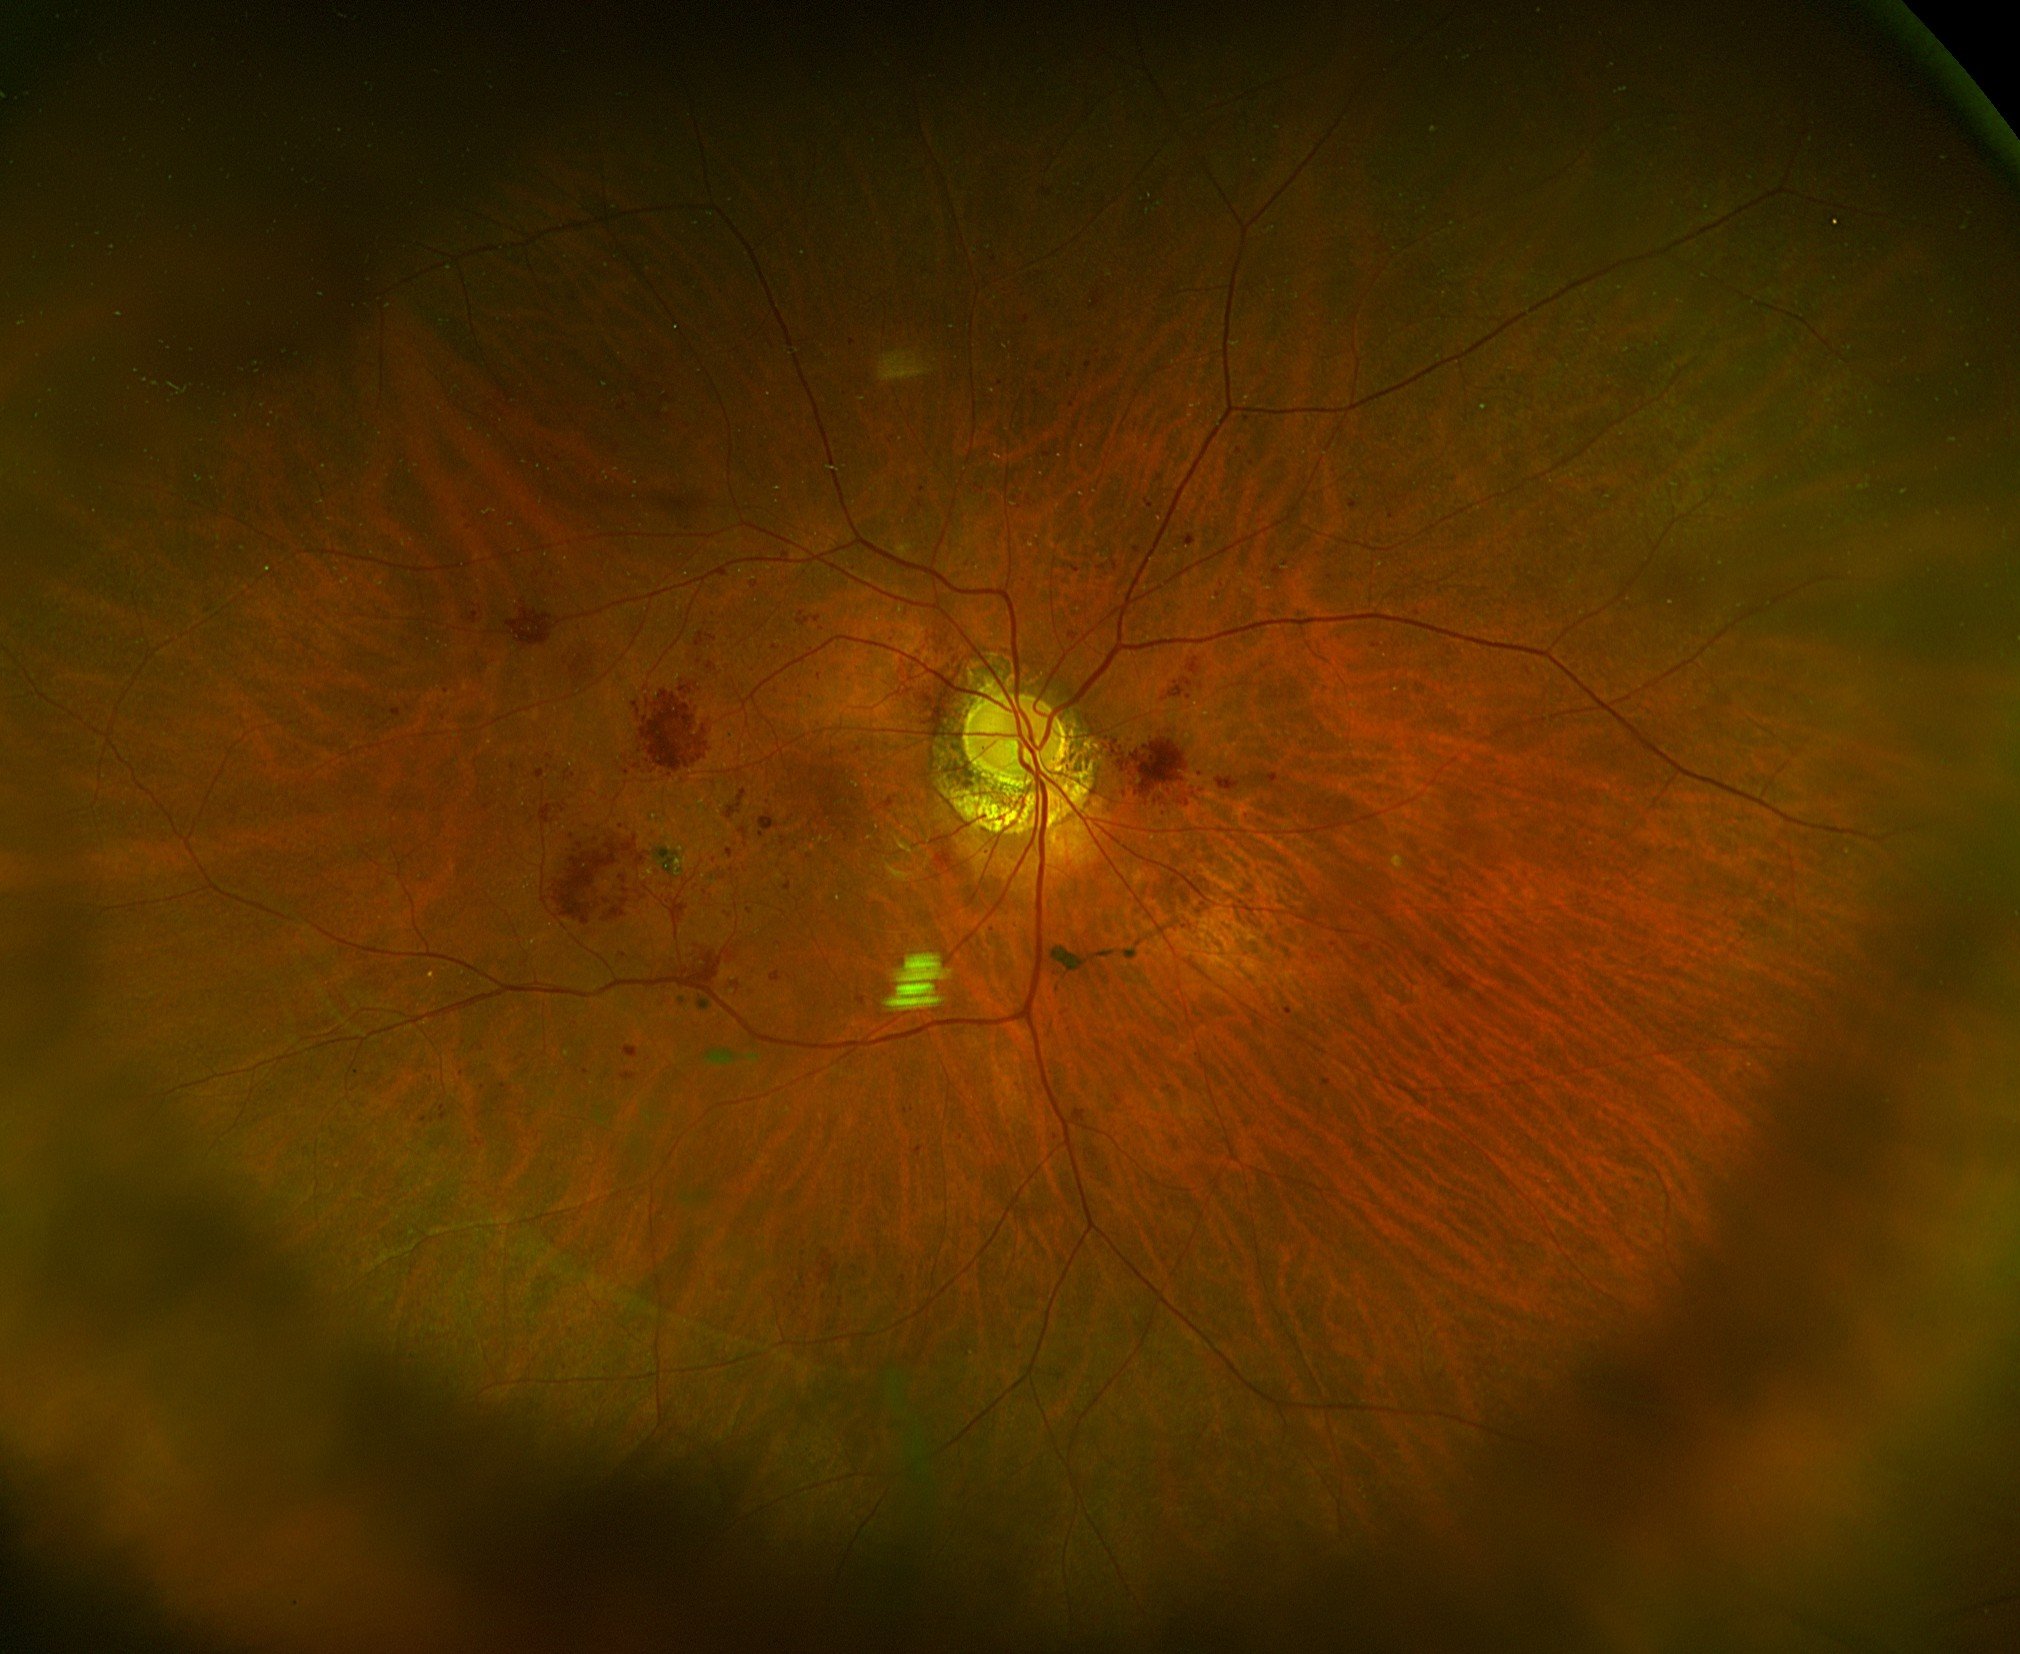

2. Elite Imaging: Our technicians capture Ultra-Widefield Fundus Photos and Macular OCT (cross-sectional imaging).